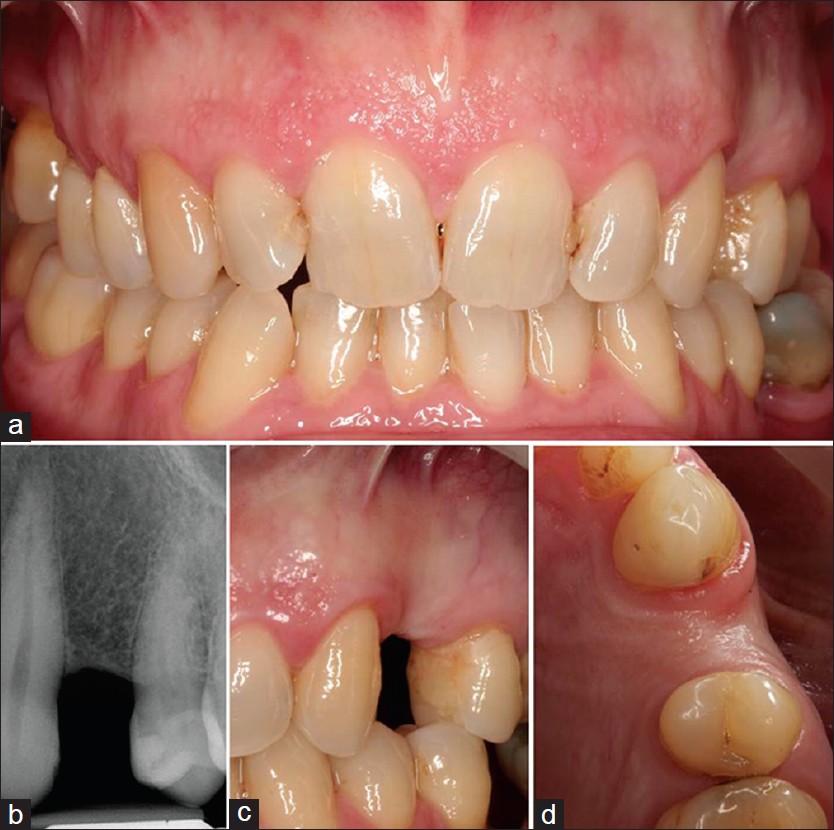

Dental restoration induced orofacial pain and its management |

Xiuxin Liu, Hans S Malmstrom, Ross Tallents DOI:10.4103/2278-9626.149683 Dental procedure induced pain may develop into a chronic condition that accompanied with functional or neuropathy changes in the nerve system. In this case, severe persistent pain gradually developed after repeatedly placing a subgingival amalgam restoration in the right second molar. Hyperalgesia and allodynia were present at the affected region. A provisional diagnosis of chronic orofacial pain with peripheral and central sensitization was considered. After re-contouring, local debridement and occlusal adjustment the pain disappeared. The underlying mechanism in this case is neuronal sensitization and peripheral Aβ-fiber mechanoreceptor activation. Its diagnosis and management depend on identification and treatment of the cause for pain generation and sensitization. |